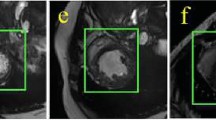

Encoder-decoder architectures are widely adopted for medical image segmentation tasks. These models utilize lateral skip connections to capture and fuse both semantic and resolution information in deep layers, enhancing segmentation accuracy. However, in many applications, such as images with blurry boundaries, these models often struggle to precisely locate complex boundaries and segment tiny isolated parts due to the fuzzy information passed through the skip connections from the encoder layers. To solve this challenging problem, we first analyze why simple skip connections are insufficient for accurately locating indistinct boundaries. Based on this analysis, we propose a semantic-guided encoder feature learning strategy. This strategy aims to learn high-resolution semantic encoder features, enabling more accurate localization of blurry boundaries and enhancing the network’s ability to selectively learn discriminative features. Additionally, we further propose a soft contour constraint mechanism to model the blurry boundary detection. Experimental results on real clinical datasets demonstrate that our proposed method achieves state-of-the-art segmentation accuracy, particularly in regions with blurry boundaries. Further analysis confirms that our proposed network components significantly contribute to performance improvements. Experiments on additional datasets validate the generalization ability of our proposed method.